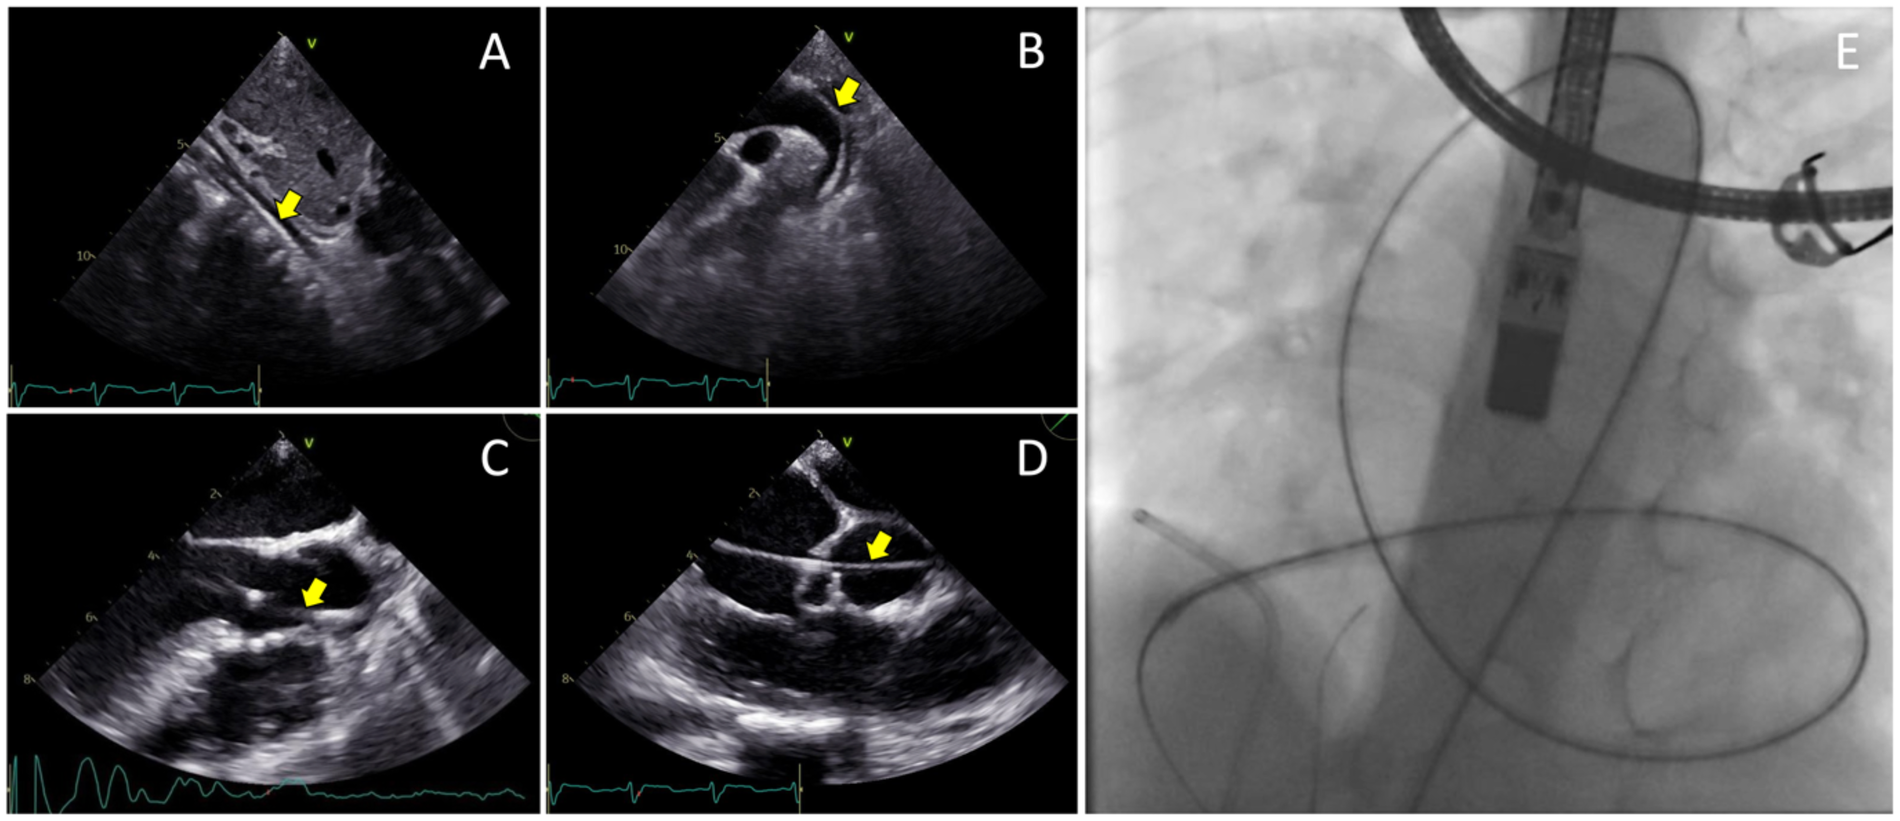

The femoral vein was punctured, and a 5F sheath was inserted. Guided by TTE and TEE, a JR Guiding catheter 3.5/5F assisted by 0.035” soft hydrophilic wire was introduced from the femoral vein into the inferior vena cava, and into the right atrium. The catheter was directed at the jet turbulence to cross the tricuspid valve defect. Despite several trials, including switching to a Multipurpose side hole catheter, this approach remained unsuccessful. An alternative via the right femoral artery was then attempted. The catheter was inserted through the aorta, to the left ventricle, which successfully crossed the tricuspid valve defect directed at the right atrium, before being advanced further into the inferior vena cava. Konar-MF VSD Occluder No. 6/8 mm was deployed through the catheter and advanced until it reached the tip of the catheter (Figure 3). The low-pressured disc was placed at the right atrium. The whole system was then pulled into the site of the LV-RA connection, and the high-pressured disc was placed at the left ventricle ends to properly seal the defect (Figure 4).

Figure 3

Transesophageal echocardiography views of the 0.035” soft hydrophilic wire (yellow arrows) being advanced from the femoral artery (A) into the abdominal aorta, (B) through the descending aorta and aortic arch, (C) into the left ventricle, (D) and crossing the tricuspid valve defect. (E) Fluoroscopy view of the Terumo wire after crossing the site of defect.